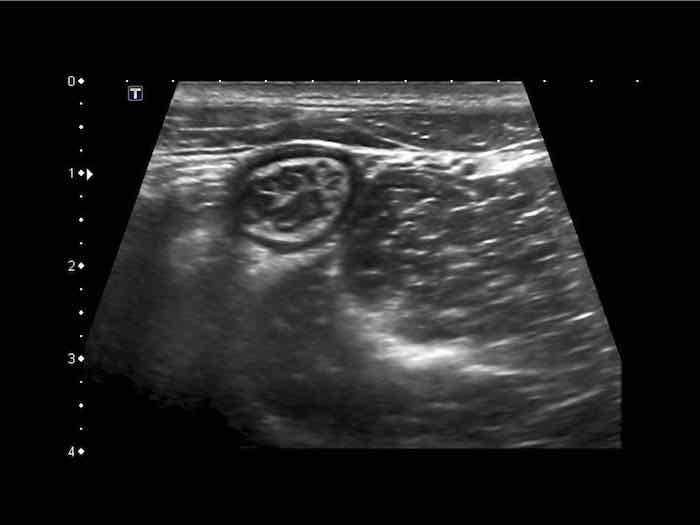

Đây là hình ảnh siêu âm của một trẻ 2 tuổi bị lồng ruột hồi manh tràng từng đợt, được khám trong khoảng thời gian giữa các cơn.

Hồi tràng với nhiều mảng Peyer sa vào manh tràng.

Hình ảnh siêu âm kinh điển của lồng ruột hồi-manh tràng ở hai trẻ khác nhau.

Trong cả hai trường hợp, đoạn hồi tràng bị lồng được định vị không đối xứng bên trong ống lồng ngoài, do mạc treo ruột tăng âm có chứa mỡ, bám vào hồi tràng và đi theo hồi tràng khi bị kéo vào trong.

Trong mạc treo, siêu âm cho thấy một hạch bạch huyết mạc treo (hbh) phóng đại ở cả hai.

Các hạch này phì đại như một phần của tình trạng tăng sản hạch bạch huyết toàn thân và khônghu trú trong lòng hồi tràng.

Do đó đây không phải là điểm dẫn đầu nguyên phát. Ở bệnh nhân bên phải, ruột thừa (mũi tên) cũng bị kéo vào trong.

Lưu ý cấu trúc đa lớp của thành bụng phía trước của phức hợp lồng ruột, đại diện cho ba lớp thành ruột bị gấp lại.